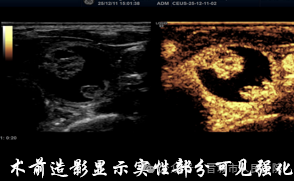

手术当天,在超声实时监控下,医生将消融针精准穿刺至结节中心。术前造影清晰勾勒出结节边界,如同 “导航定位” 一般,确保针尖精准避开正常甲状腺组织和喉返神经等关键结构。随后,消融针释放高温能量,将结节组织 “原位灭活”,整个消融过程仅用时2分34秒!

术后即时造影显示,原本高增强的结节区域已完全 “无血供”,这意味着病灶已被彻底消融。张先生的脖子上,只留下一个毫米级的针眼,按压片刻后便无明显痕迹。术后他生命体征平稳,没有出现疼痛、肿胀等不适症状,第二天就顺利出院回家。